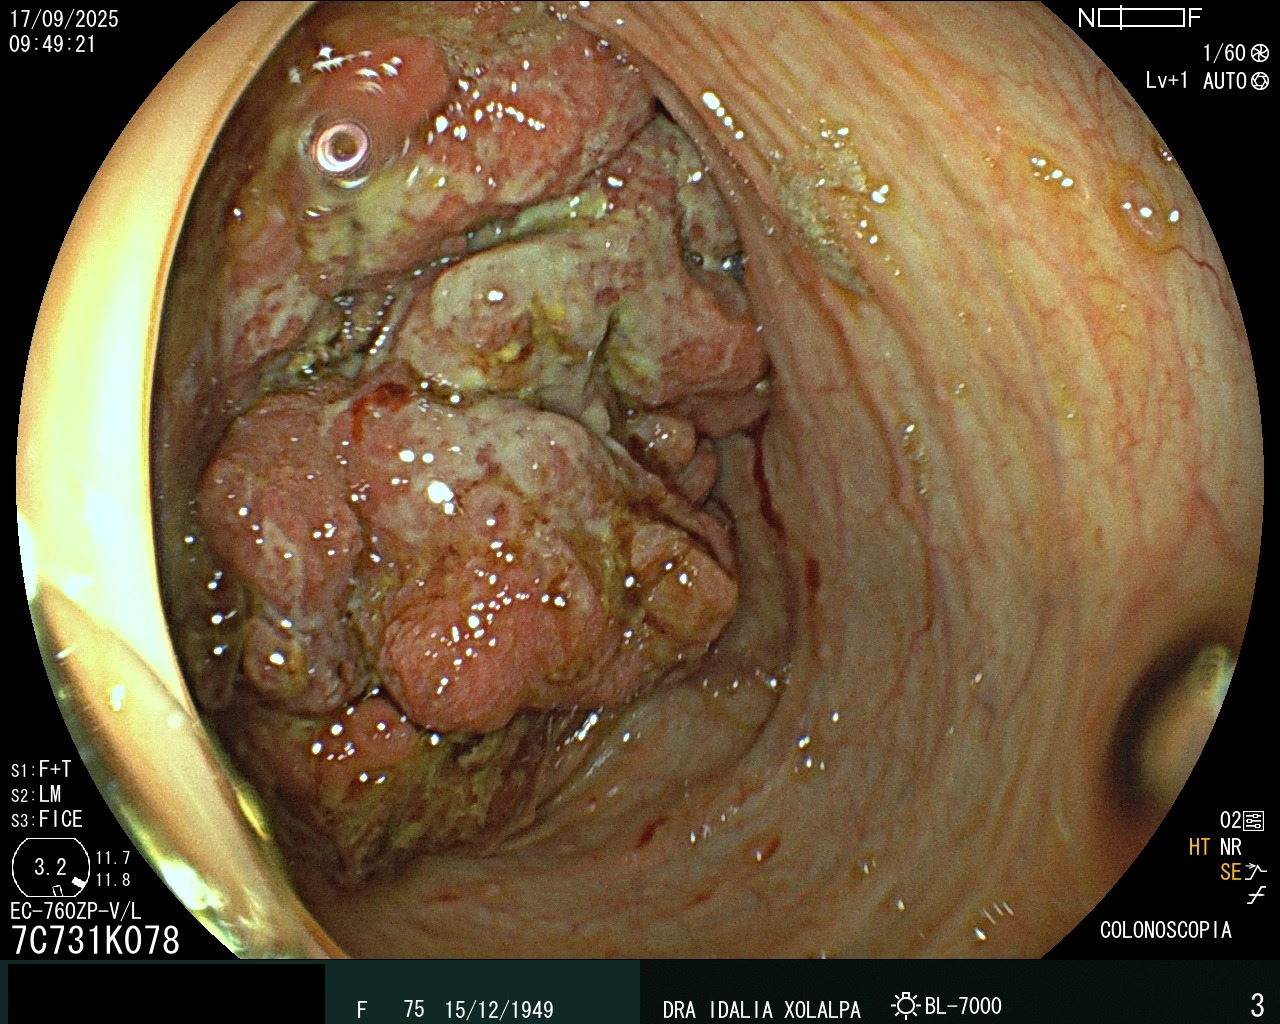

Detección de Tumores

Detección temprana de tumores en colon